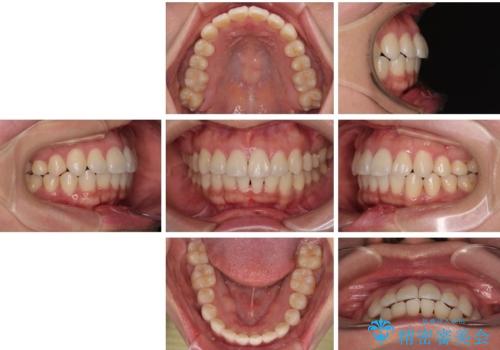

「歯並びと正中が整って、自信をもって笑えるようになった」

と大変ご満足のお言葉をいただきました。